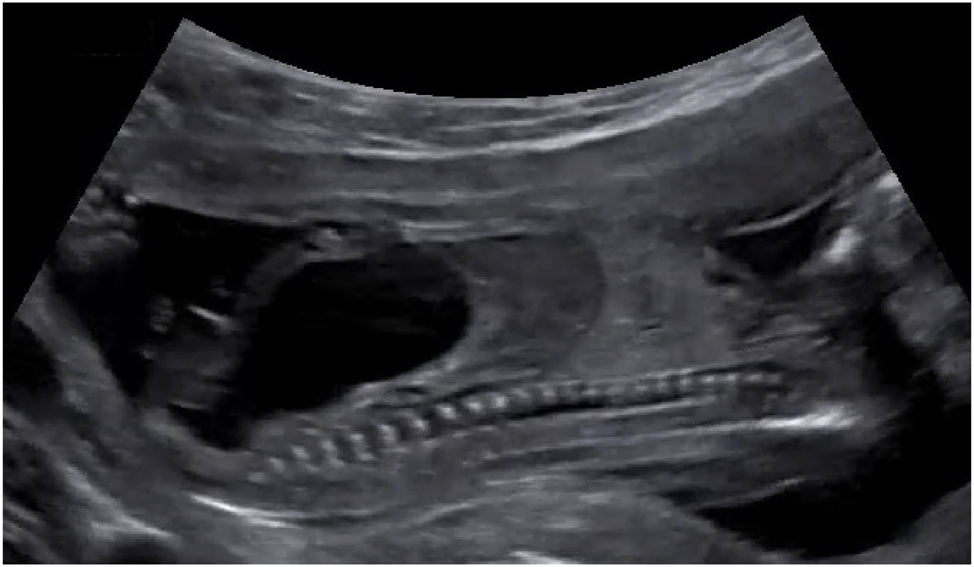

1. aCritically abnormal Doppler measurements is defined as umbilical artery Doppler with absent or reverse flow in end-diastole and/or ductus venosus Doppler with reverse a-wave (Figure 1) or and/or umbilical vein with pulsatile flow.

Figure 1:

Ultrasound findings relevant for TTTS staging. (A) Umbilical artery Doppler with reverse flow in end-diastole and (B) ductus venosus Doppler with reverse a-wave. (C) Hydropic fetus with ascites and skin oedema.